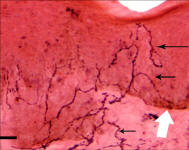

of the Equine Foot

A New 464 Page Textbook, in Full-Color with 630 Pictures and Drawings, by Pete Ramey

A Few Pictures from the book:

Only 570 pictures yet to see... but you get the idea.

Photos referenced in text from Bidwell/Bowker, Bowker, Clayton, Cowles, Hampson, Kellon, Ramey, Ridgway, Sullivan, Taylor, Watts.